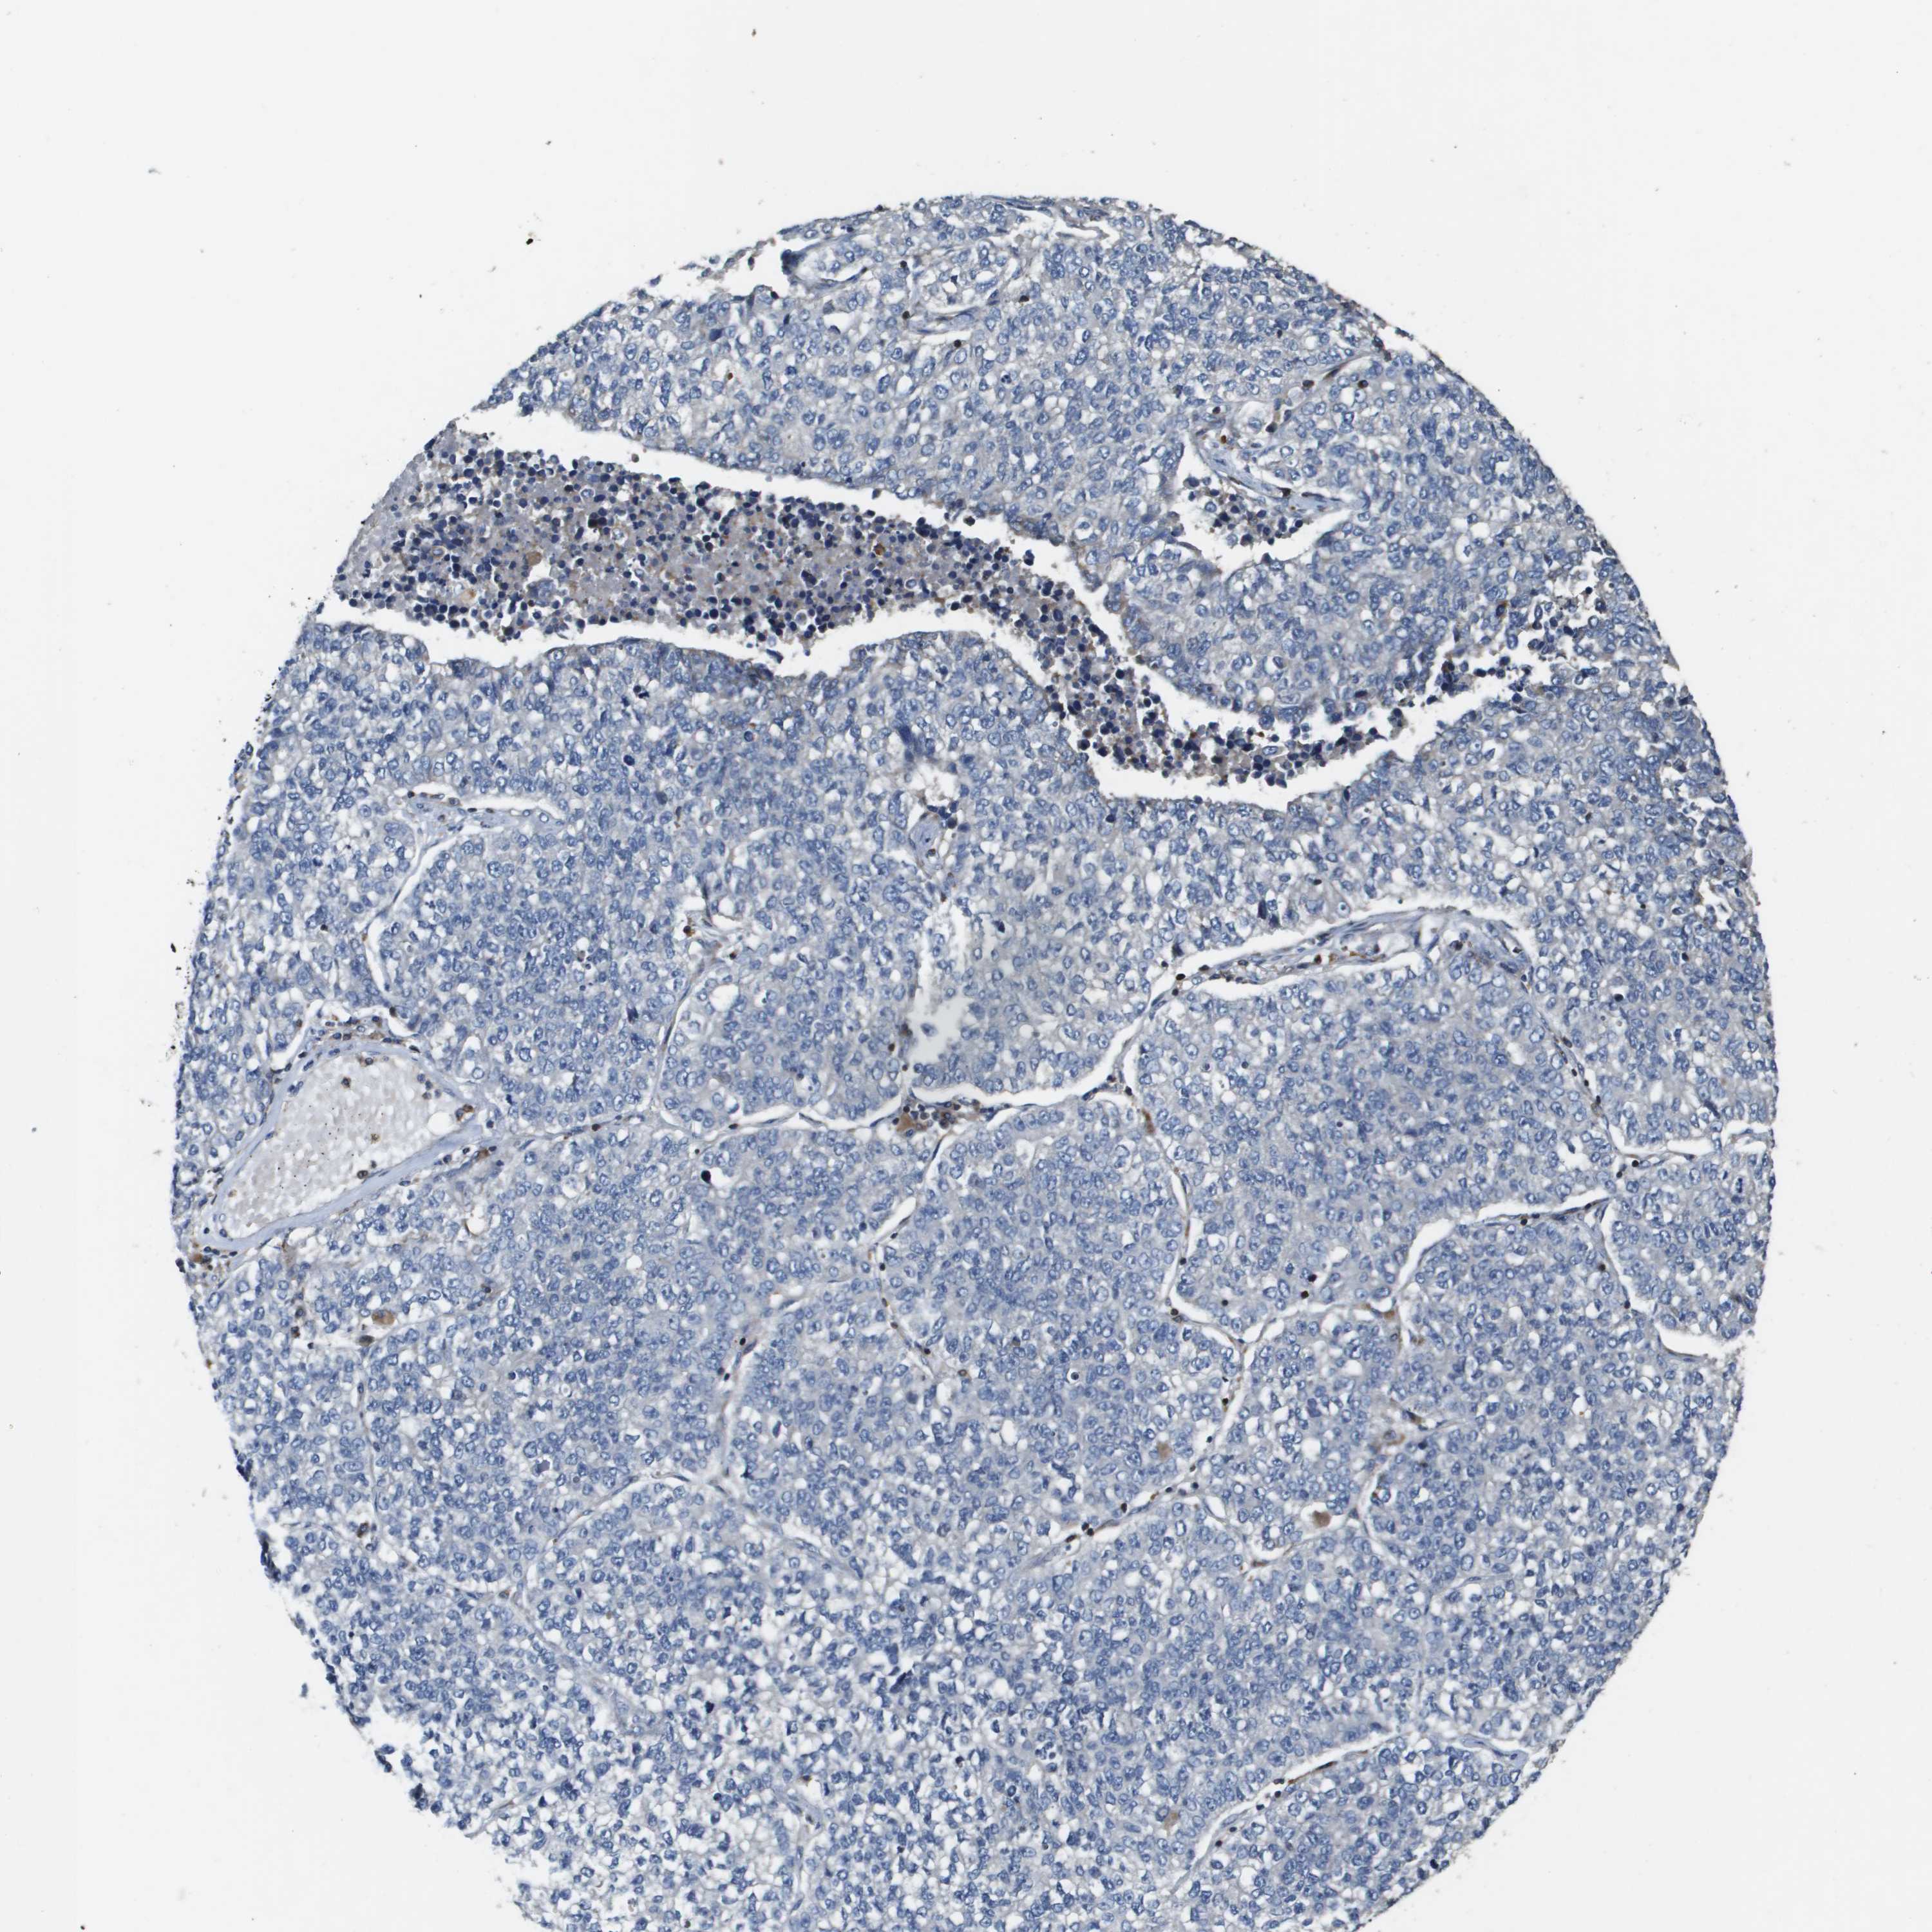

CANCER LUNG CANCER Show tissue menu

SCN4B is potential prognostic, high expression is favorable in Lung Adenocarcinoma (TCGA)

SCN4B is not prognostic in Lung Adenocarcinoma (validation)

SCN4B is not prognostic in Lung Squamous Cell Carcinoma (TCGA)